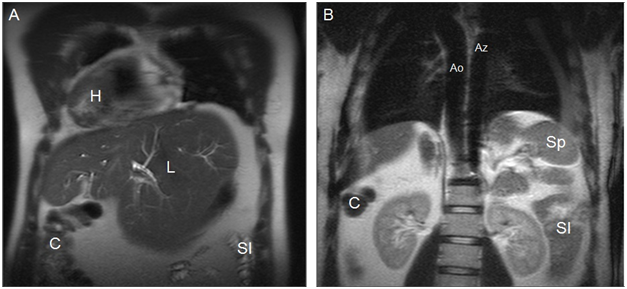

The most consistent anatomic finding is an interrupted suprarenal IVC11 with azygous or hemiazygous continuation, with direct hepatic drainage to the heart chambers through a common trunk. In polysplenia, both lungs are bilobed with hyparterial bronchi. Cardiac anomalies in polysplenic patients are less severe16 and less common (50-90%) than in patients with situs with asplenia. Partial anomalous venous return to the lungs, atrial septal defect, and atrioventricular canal are the most common cardiac anomalies.9 In addition, these patients have a higher risk of developing arrhythmias-as a result of the absence of the sinus node, located in the left atrium-and complete heart block.12 On the other hand, in patients with heterotaxy syndrome with polysplenia the liver and gallblader are susally located next to midline (Figures 3-5).10,14

Figure 4Coronal MR images in a more anterior position (A) and in a more posterior position(B) show dextrocardia and cardiac apex on the right (H), midline liver (L) with a prominent left lobe, colon on the right (C), small intestine on the left (SI), aorta on the right (Ao), azygos vein on the left (Az), and one splenule on the left (Sp). IVC cannot be identified. Cholecystectomy.

Dextrocardia with cardiac apex to the right (Figures 4) (Figure 8).

2. Aorta on the right with aortic arch over the right bronchus (Figures 3, 4, 6, 7 & 8).

3. Polysplenia with splenunculi on left side (Figures 3, 4 and 5).

4. Direct hepatic drainage to the atrium through a common trunk due to the absence of the hepatic segment of IVC (Figures 3 & 4).

6. Venous drainage from the abdomen is carried by the azygos system (azygos vein to the left of the thoracic aorta). Azygos arch is over the left bronchus (Figures 3, 4 & 8).

7. Intestinal malrotation: the duodenum does not pass between the aorta and the superior mesenteric artery, Treitz’s angle is not visualized, the colon lies in the right hemiabdomen, and the small intestine in left hemiabdomen (Figures 4-6).

9. Midline liver with a prominent left lobe (Figures 3-5).